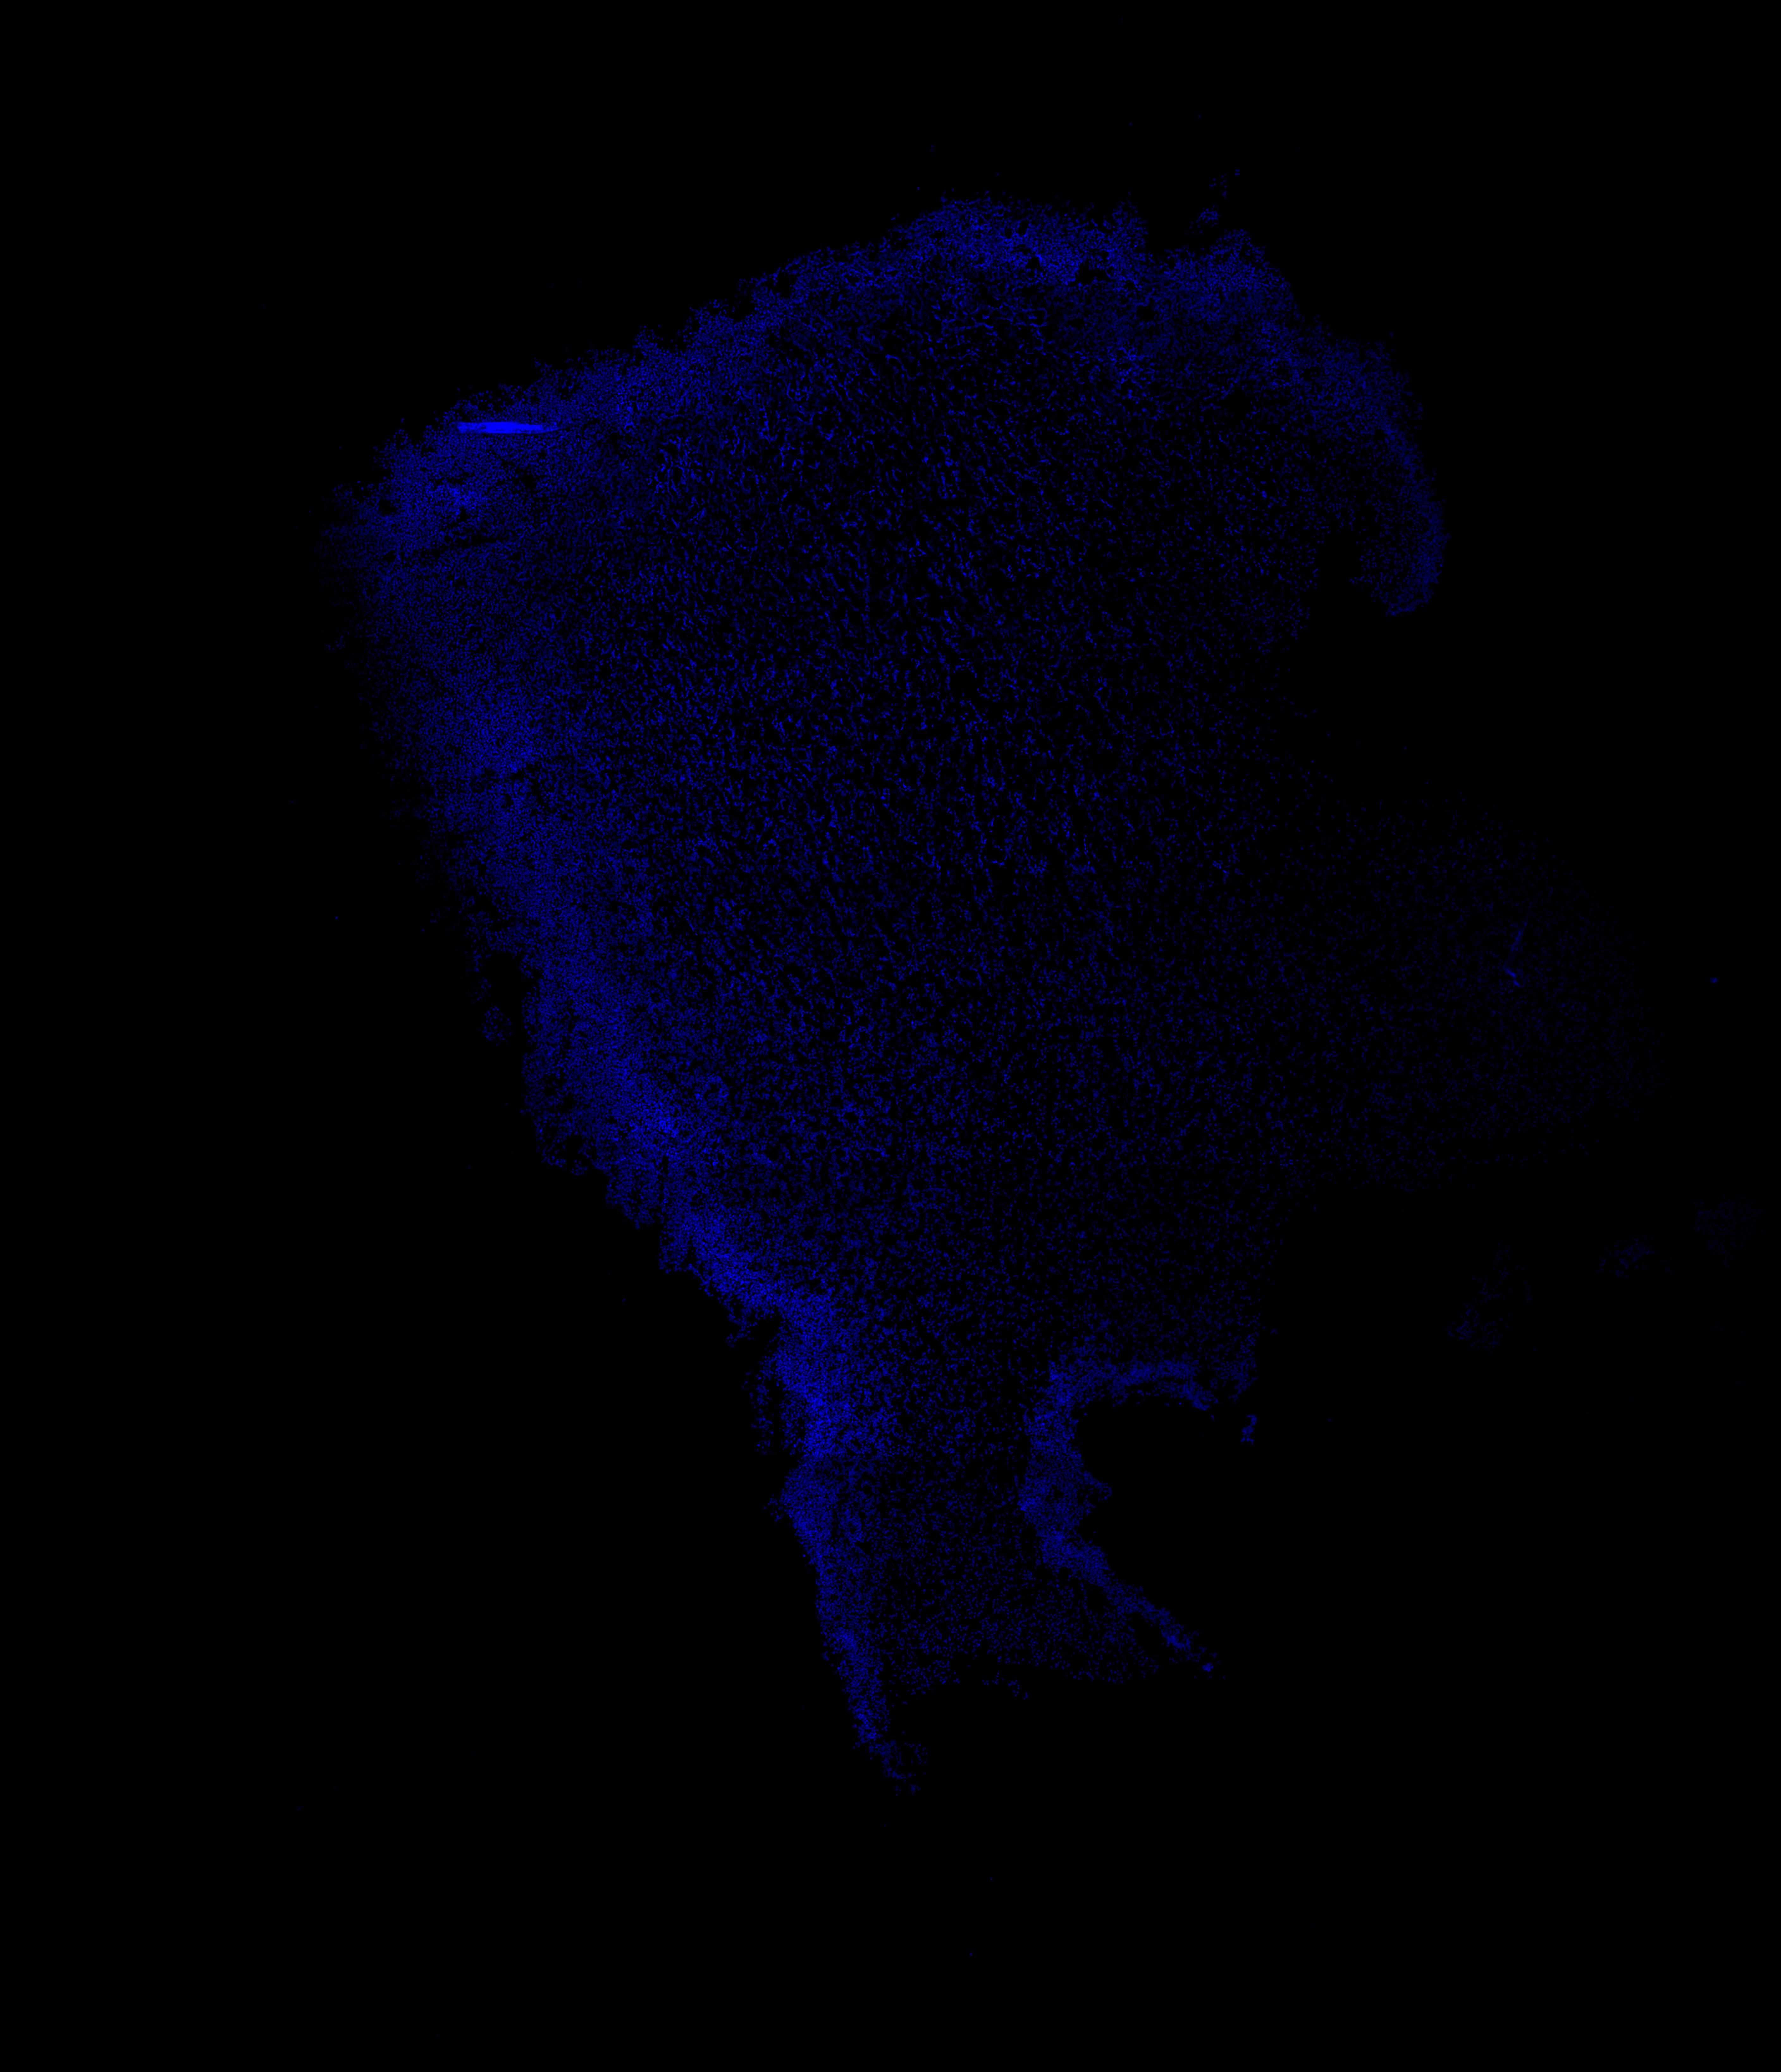

An anatomical analysis of the developing human midbrain from 6 post-conceptional weeks (PCW) to 22 PCW reveals increased tissue complexity, characterized by the emergence of dopaminergic nuclei, as highlighted by immunofluorescence analysis for tyrosine hydroxylase (TH).

DAPI

22PCW human midbrain